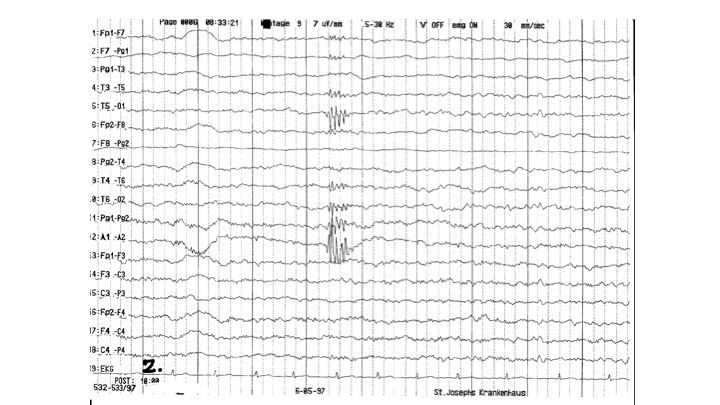

Artefakte im EEG | 36.65 zurück | weiter